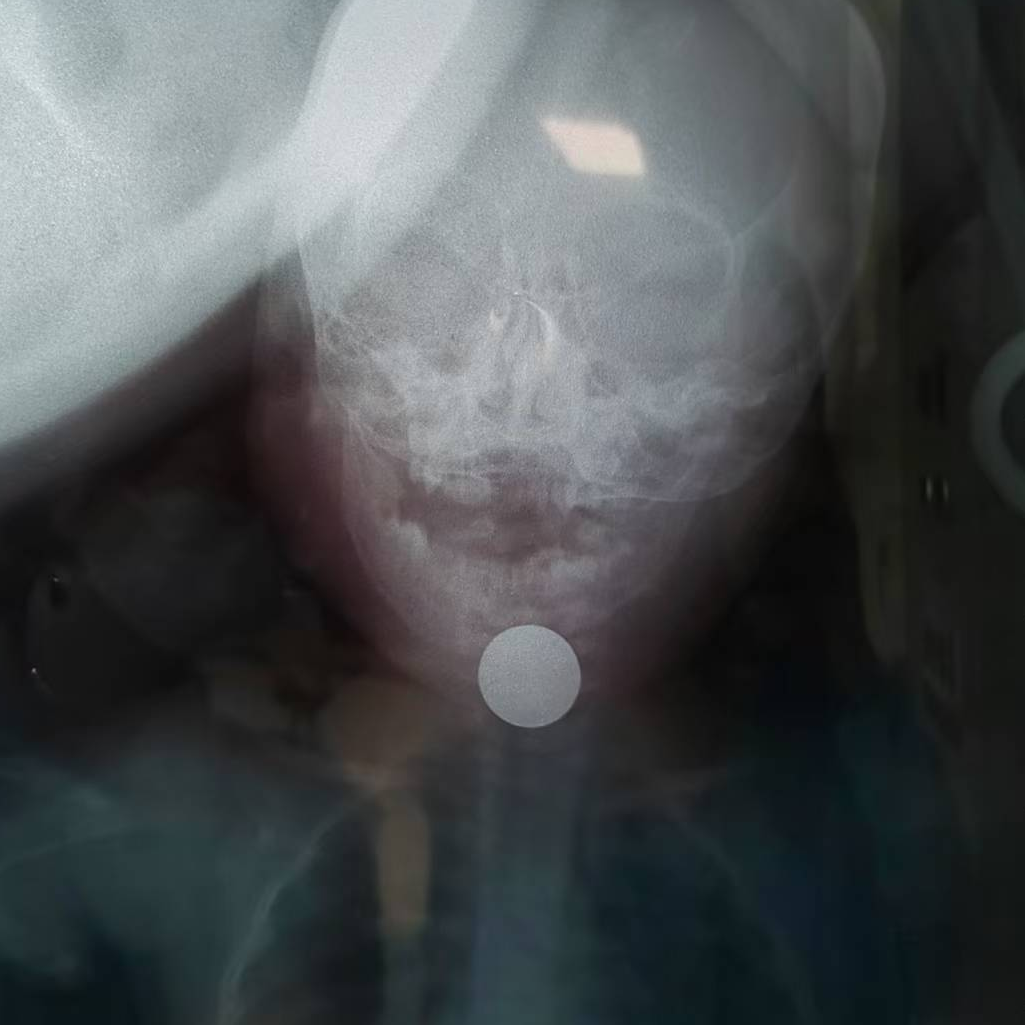

DR检查结果显示,硬币直径达2.5厘米,卡在食管胸上段,情况万分危急,若不及时取出,可能导致食管穿孔、气管食管瘘甚至造成破裂危及生命。消化内科主任马西强面色凝重:“常规方法需全身麻醉联合多科室手术,但硬币位置特殊,操作风险极高!”